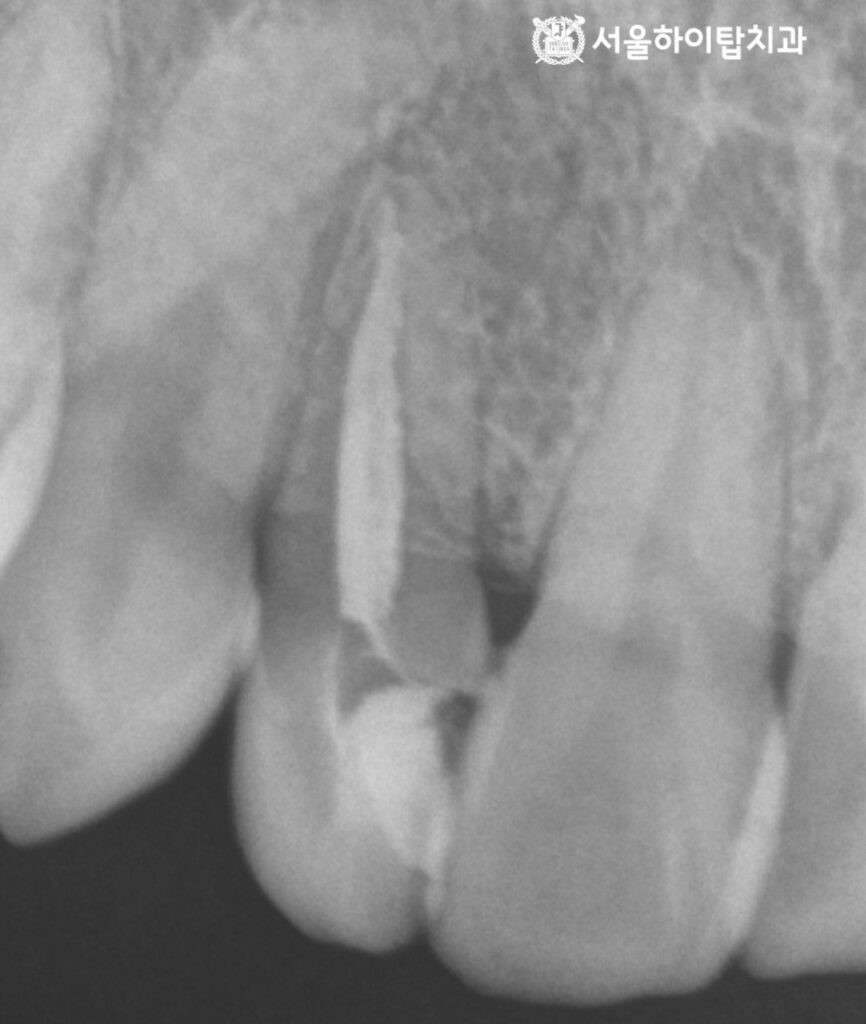

4. 쉐이드 테이킹(Shade taking)

마지막으로,

새로운 크라운으로 덮기 위해

훼손된 치아의 형태를 다듬는

prep 과정을 진행합니다.

형태가 정리되면,

쉐이드 테이킹(shade taking)을 통해

주변 치아와 어울리는 색을 선택합니다.

알맞은 색상이 선택되면

인상채득을 통해 맞춤형 보철을 제작하여

연결해 주면 모든 진료 과정은 종료됩니다.